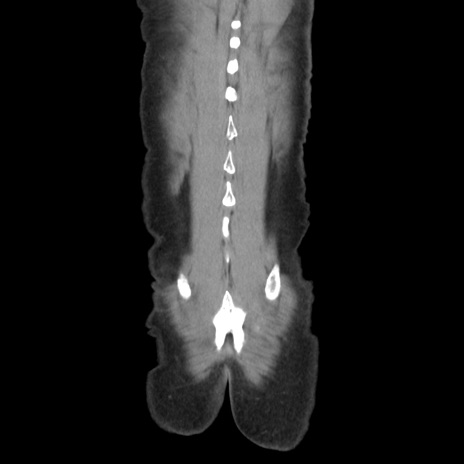

症例37(冠状断像)

【症例】40歳代 男性

【主訴】腹痛

【現病歴】4時間ほど前に電車に乗車中に臍部上より腹痛出現。徐々に増悪し起立困難となり、救急外来受診。生ものは数日食べていない。今朝お雑煮を食べた。

【身体所見】BT 36.8℃、BP 117/84mmHg、HR 91/min、SpO2 97%、苦悶様、腹部:臍上部広範囲圧痛あり、反跳痛±

【データ】WBC 8100、CRP 0.03